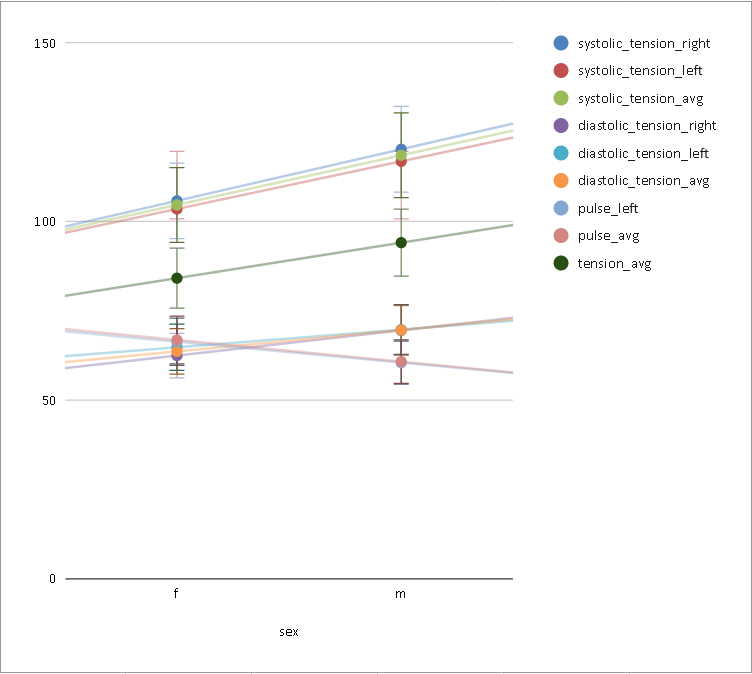

CVR and blood pressure

Due to its nature as homeostatic and cerebrovascular process, CVR is modulated by systemic changes in blood pressure¹

1. Fierstra et al. 2013 (J. Physiol.); 2. e.g. Hetzel et al. 1999 (Stroke)

Previous studies with Transcranial Doppler Ultrasound suggest to take into account blood pressure when measuring CVR²

To our knowledge, the impact of blood pressure on BOLD-fMRI based CVR estimation has not been assessed yet

EuskalIBUR

10 neurotypical subjects

(5F, age 25-40y) (3 discarded)

10 sessions, one week apart, same time of the day

Vital signs (VS), measured before the MRI session, while the subject was lying supine on a bed, once on the left arm and once on the right arm:

- Cardiac pulse

- Blood pressure (systolic and diastolic)

We averaged the two measurements and computed the Mean Arterial Pressure (MAP) and the Pulse Pressure (PP):

Correlation between VSs

Correlation between VSs

Results: blood pressure

Results: sex

- Females show higher CVR than males in most of the GM

- Previous studies report CVR higher in females¹, in males², or no differences between the two³

- A possible cause of this difference might be related to hormonal changes during the menstrual cycle

1. Kastrup et al. 1997, 1998 (Stroke), Tallon et al. 2020 (Exp. Psychol.); 2. Kassner et al. 2010 (J. Magn. Reson. Imaging)

3. Chen et al. 2021 (Int. J. Imaging Syst. Technol.), Jiménez Caballero et al. 2006 (Rev Neurol)

Results: sex

Increased blood pressure

results in localised increases in CVR.

The sex of the participant can affect CVR too.

Take home message #2

- Stationary blood pressure changes, expressed as MAP and PP, as well as sex, impact regional CVR estimation differently across sessions and subjects

-

Dynamic blood pressure changes are expected to impact CVR estimation, hence continuous blood pressure recordings are required to assess the matter

- Future studies should expand the impact of sex on CVR estimation by assessing the impact of more defined factors (e.g. hormonal fluctuations)